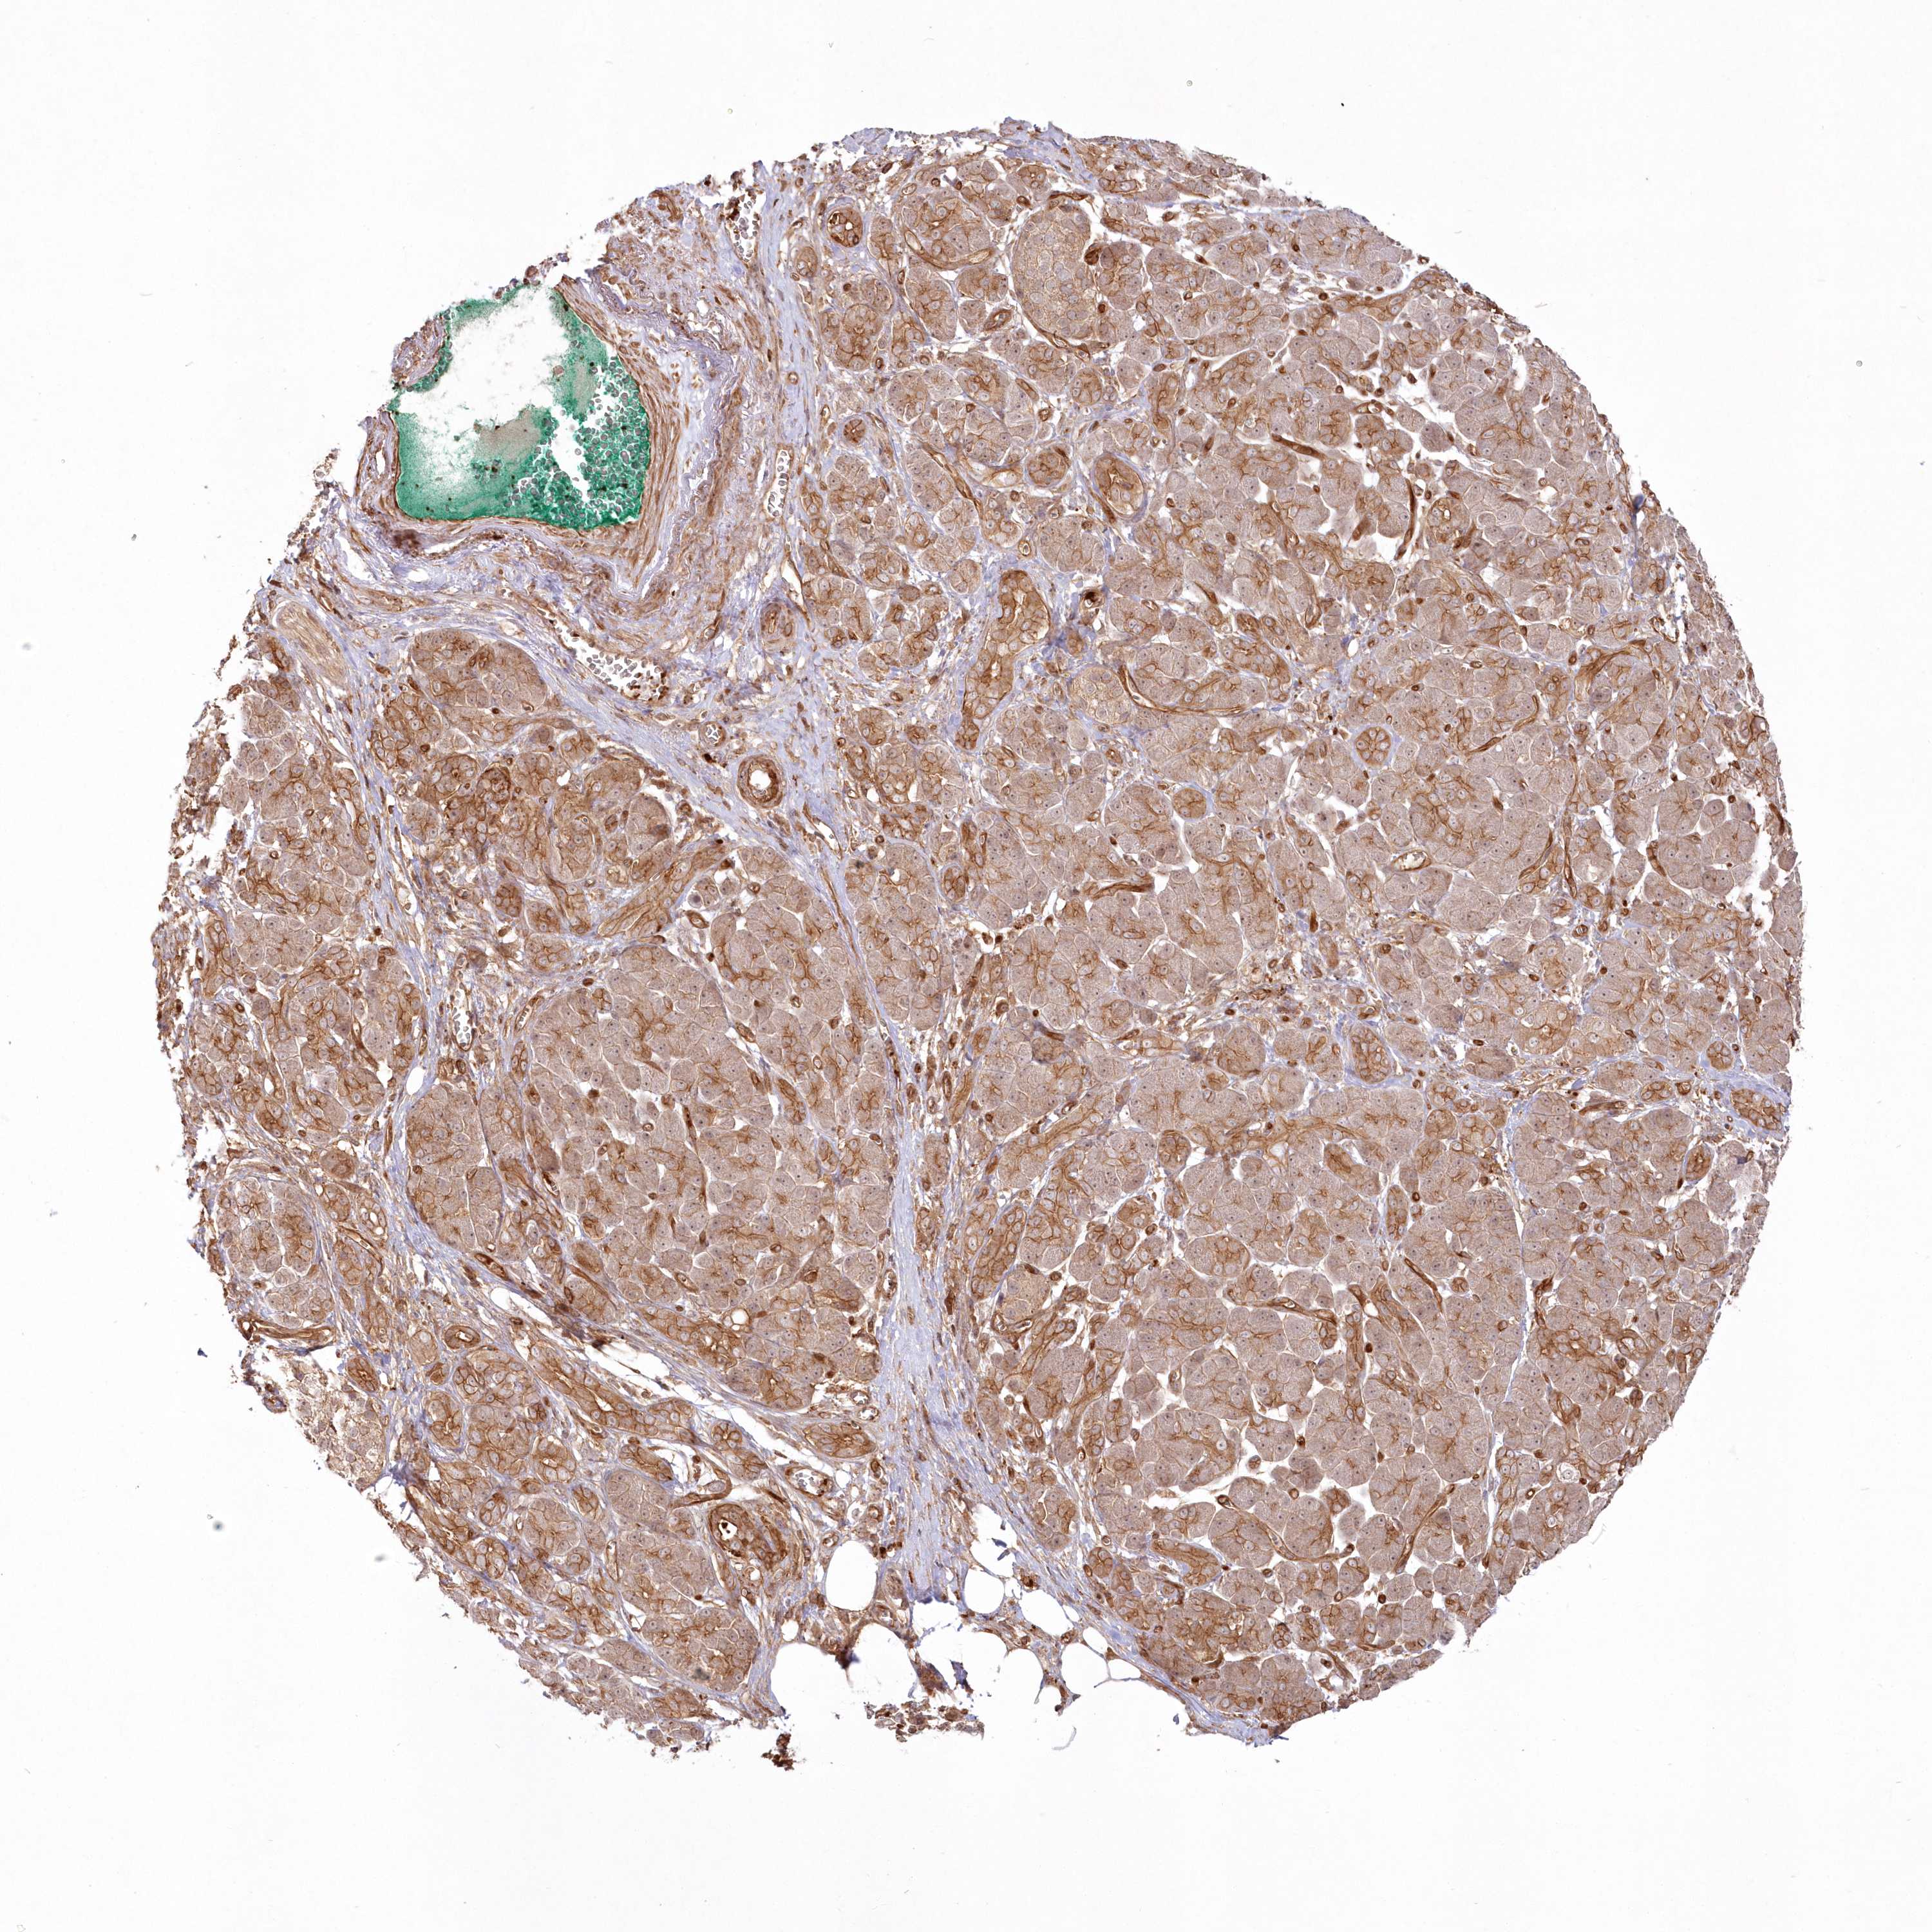

PANCREATIC CANCER - Protein expressioni

A mouse-over function shows sample information and annotation data. Click on an image to view it in a full screen mode. Samples can be filtered based on level of antibody staining by selecting one or several of the following categories: high, medium, low and not detected. The assay and annotation is described here.

Note that samples used for immunohistochemistry by the Human Protein Atlas do not correspond to samples in the TCGA dataset.

Antibody stainingi

Antibody staining in the annotated cell types in the current human tissue is reported as not detected, low, medium, or high, based on conventional immunohistochemistry profiling in selected tissues. This score is based on the combination of the staining intensity and fraction of stained cells.

Each image is clickable and will lead to virtual microscopy that enables deeper exploration of all samples and also displays staining intensity scores, fraction scores and subcellular localization as well as patient and tissue information for each sample.

Antibody HPA035638

Staining

High

Medium

Low

Not detected

Intensity

Strong

Moderate

Weak

Negative

Quantity

>75%

75%-25%

<25%

None

Location

Nuclear

Cytoplasmic/membranous

Cytoplasmic/membranous,nuclear

Adenocarcinoma, NOS